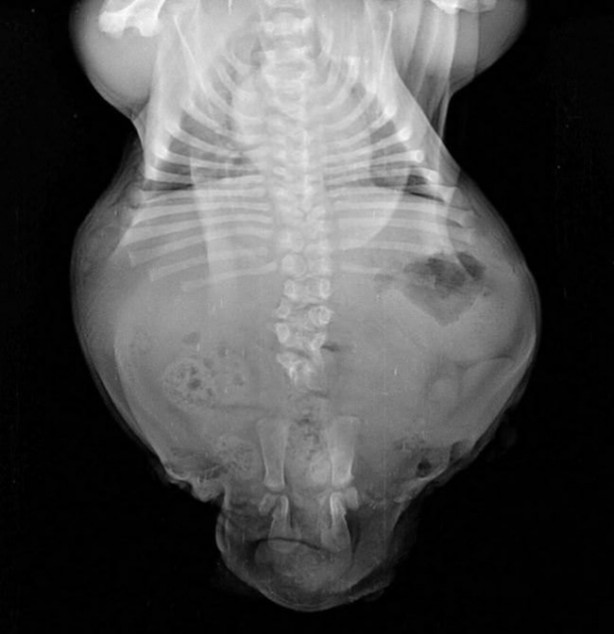

Küçük Bonsai, 2 topal bacağı ve diğer birçok doğum kusurları ile yeni doğmuş bir köpek.

Arka 2 bacağı topal olduğu için zorlanan bu minik köpek için hayat zorlaşınca çözüm olarak operasyona alındı.

Geçirdiği operasyon ile topal olan bacağı alınan Küçük Bonsai, geçirmesi gerek diğer operasyonlar için gün bekliyor.

Küçük Bonsai ameliyatla alınan 2 bacaktan sonra ön bacaklarını daha da zorlamaya başladı.

Bu durumun minik köpeğin kısa ve çarpık omurgasını kötü etkilediği söyleniyor.